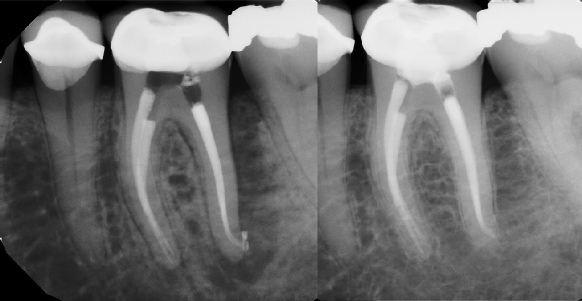

Pre-op Post-op 6 mos.